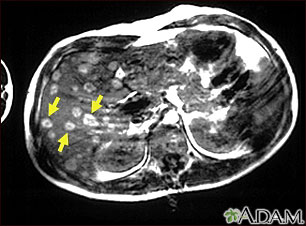

Esta IRM de la parte superior del abdomen muestra tumores múltiples en el hígado que se han diseminado (metástasis) desde un melanoma maligno en un brazo o pierna. Observe las áreas circulares y claras presentes en todo el hígado (en su mayoría ubicadas del lado izquierdo de la pantalla).